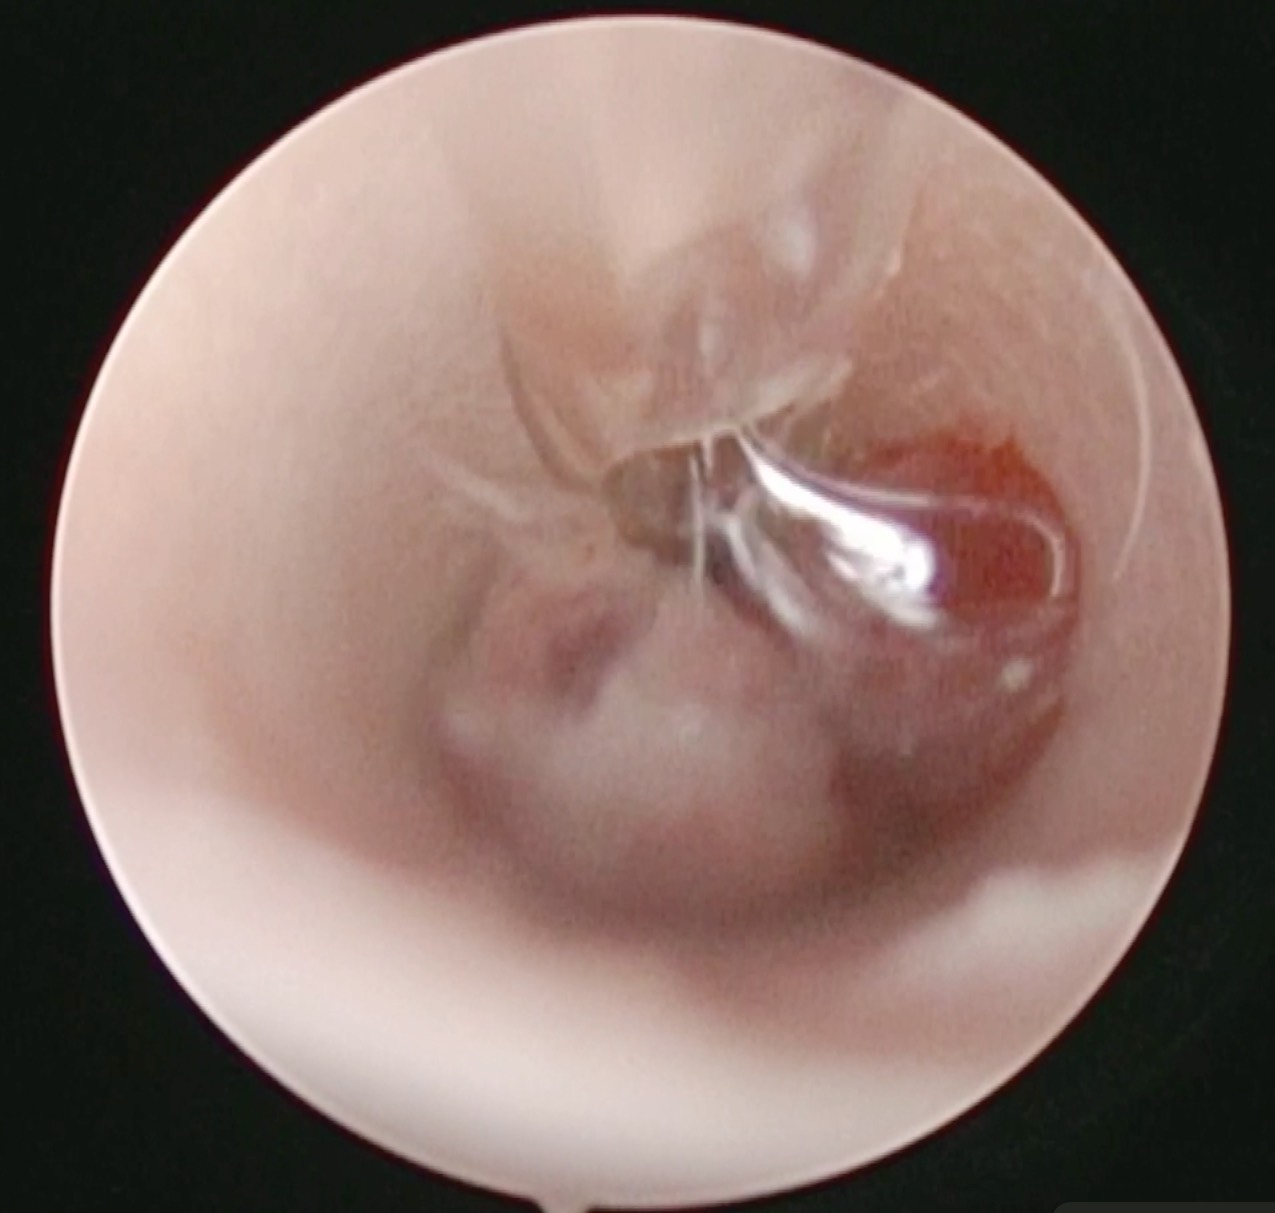

切除できそうなものなのかオトスコープで判断することができます。

耳の腫瘤が原因で膿が出ている場合はいくら耳の洗浄をしても改善することはありません。

切除などの根本解決をしなければいけないということですね。

腫瘤を摘出した様子